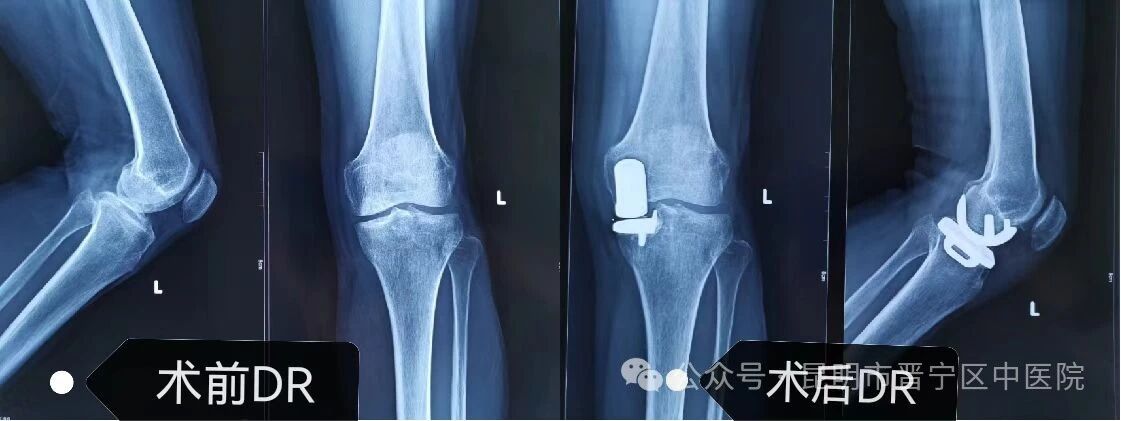

术前DR摄片 术后DR摄片